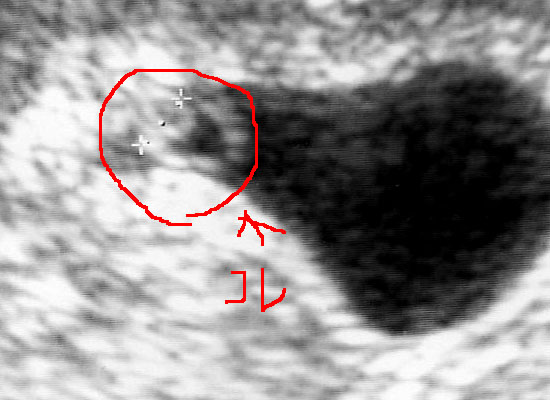

『胎のうがうっすらと確認出来る程度なんで、まだはっきりとわからない』と言われてたんですね。

しかしとりあえず、丸い粒は見えて着床してるって事はわかったんで、旦那には『育つかどうかわからんけどとりあえず出来てるっぽい』と説明しときました。